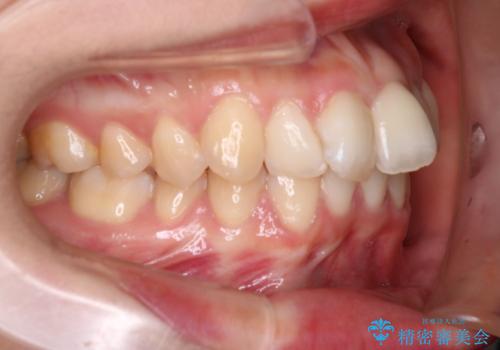

抜歯矯正×インビザライン|上下のバランスを整え、美しい歯並びへ

- 患者様は、上下の噛み合わせのバランスが悪く、特に上顎の前歯の突出を気にされて来院されました。診査の結果、下顎の歯並びに合わせて上顎を後方へ移動させる必要があると判断し、上顎の小臼歯2本を抜歯することを提案しました。目立たない矯正を希望されたため、**インビザライン(マウスピース矯正)**を選択。計画的にスペースを作りながら、バランスの取れた歯並びを目指しました。

治療はまず、上顎の小臼歯を2本抜歯し、そのスペースを利用して前歯を後方へ移動させました。インビザラインはアタッチメントを併用し、より効率的に歯を動かせるよう調整。定期的なチェックとアライナーの交換を続け、約3年かけて理想的な歯並びと噛み合わせを実現しました。治療後はリテーナーを使用し、安定した状態を維持。患者様からは「口元がスッキリし、横顔の印象も変わった」と嬉しいお声をいただきました。